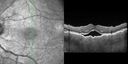

75 year old man with 2 weeks of vision loss in both eyes. He has serous retinal detachments and choroidal effusions more in the left eye than the right eye. He has been getting every 3 week testosterone shots for 1.5 years. He was at a weight loss clinic from 6 to 3 months ago and had Lipo-B shots and lost 35 lbs. He also takes daily Cialis on his doctors recommendations for low testosterone. He is otherwise in good health. Vision is 20/40 right eye, 20/50 left eye. The images show the choroidal effusion with choroidal thickening. This spontaneously resolved without altering his systemic testosterone or cialis therapy over the course of about 4 months

Choroidal Effusions and Serous retinal detachment with Systemic Testosterone and Cialis in 75 year old Man450 viewsSD OCT shows choroidal thickening and subretinal fluid00000

(0 votes)